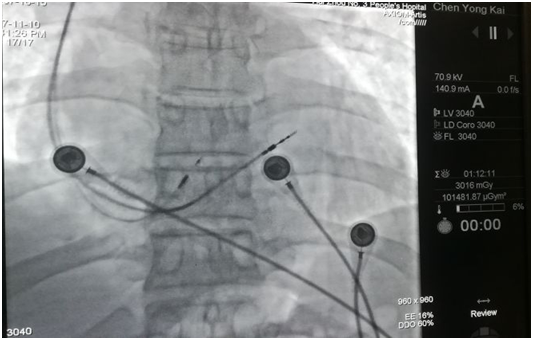

His電極及右室間隔面電極

手術(shù)當(dāng)天,楊飛副主任醫(yī)師與鐘思干主任沉著冷靜、有條不紊實(shí)施著手術(shù),首次嘗試就成功穿刺腋靜脈,順利置入血管鞘,沿鞘管送入3830主動(dòng)電極至房室交界處房側(cè),順利找到his電位。

反復(fù)多次嘗試,歷經(jīng)各種挑戰(zhàn),制定相應(yīng)對(duì)策,終于柳暗花明!電極與his點(diǎn)位緊密結(jié)合成革命伉儷,測(cè)試起搏閾值為0.4V,阻抗為460Ω,起搏心電圖如同正常心電圖,參數(shù)非常理想,甚至是超出預(yù)期的理想。